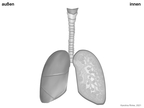

Lunge (Organ, Mensch)

Das Bild gehört zur Serie "Organe des Menschen". Das Bild verdeutlicht den Aufbau der menschlichen Lunge. Bild-Variante: Lunge mit Luftkreislauf; farbig; unbeschriftet. Es gelten die Nutzungsbedingungen der Mediothek und Pixiothek.

Lunge (Organ, Mensch)

(1024x768)

Lungenbläschen, Lunge (Organ, Mensch)

(1024x768)